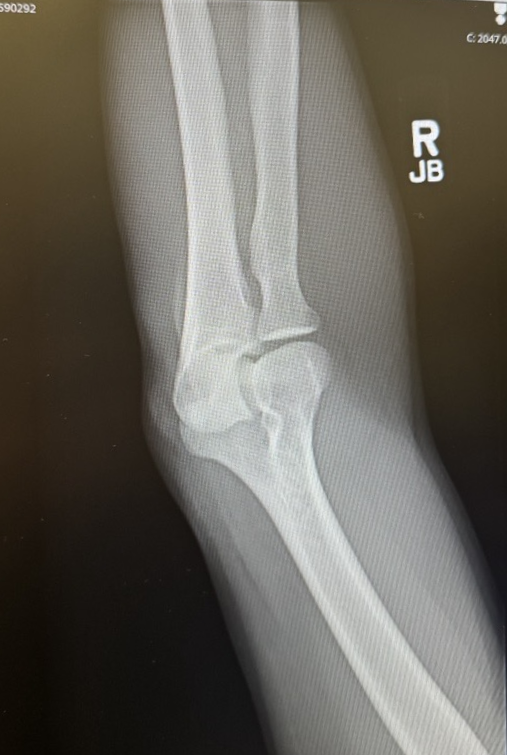

Bobbing and weaving through the trees, Larry made a split-second decision to cut right, directly in front of a gnarly birch. His momentum was carrying him one way while his board was turned another, and the next thing he knew, he was bouncing off the tree like a pinball, sending his helmet and Insta360 flying through the woods.

He walked away with a tweaked back and an elbow injury that put him in a sling for a week. Not exactly the souvenir he was hoping for.